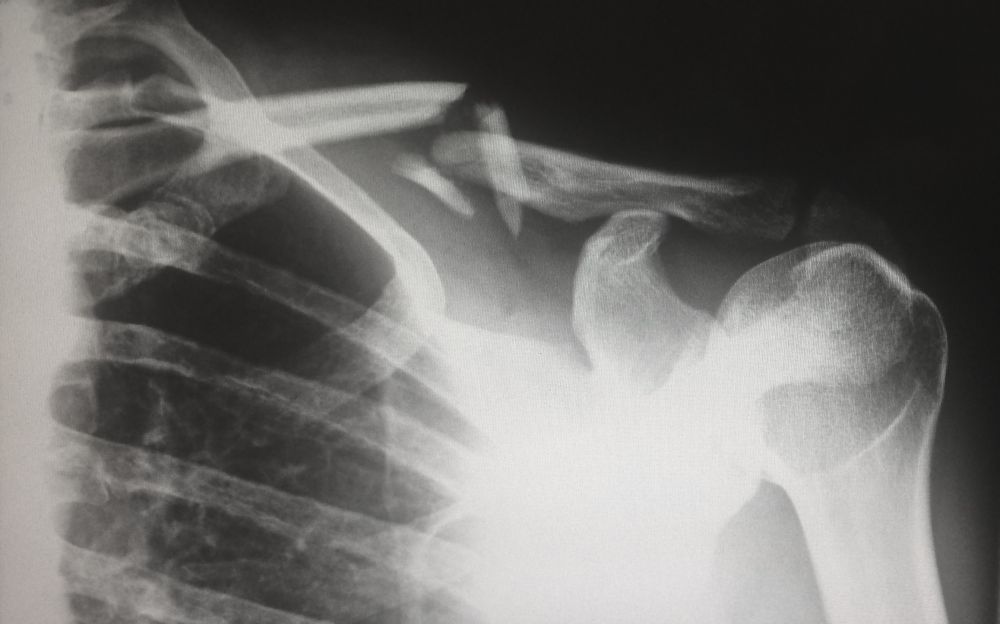

Røntgenundersøgelse

07 March 2023